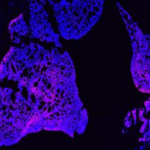

吸入式肺靶向RNA递送系统

创新构建吸入式 RNA 递送系统实现呼吸疾病治疗机制突破:针对 LNP 雾化后粒径增大、 包封率下降及难以突破黏液屏障等难题,通过脂质结构、制剂创新和制备工艺的多维协同优化,构建兼具优异的雾化稳定性、气动性能与黏液穿透性能的吸入式递送系统,在多种呼吸系统疾病模型中展现出高效的基因调控和显著的治疗效果。

代表性论文:Nature communications, 2025;Nature communications, 2025; Nature Communications, 2024(ESI高被引论文); Science Advances, 2022(ESI高被引论文)